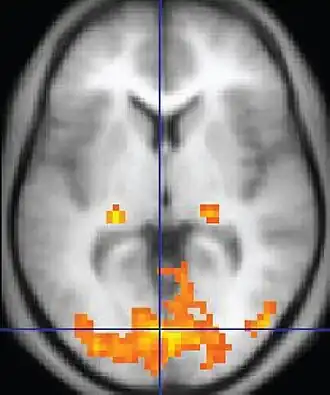

Imagem por ressonância magnética funcional oferece algumas evidências sobre as conexões e sincronizações neurais

A Síndrome de Asperger é uma condição neuropsicológica que causa efeitos no desenvolvimento cerebral em geral, provocando mudanças nos vários sistemas funcionais existentes.[54] Embora a dissociação da SA com outros transtornos do espectro do autismo ainda não seja clara e não tenha sido descoberta nenhuma patologia em comum para todos os distúrbios,[36] há probabilidade de que a síndrome tenha mecanismos distintos das demais desordens.[55] Alguns estudos neuroanatômicos e supostas ações de agentes teratogênicos presumem que a alteração no desenvolvimento cerebral ocorra logo após a fecundação.[52] A migração anormal de células embrionárias durante o desenvolvimento fetal pode afetar a estrutura definitiva do cérebro e seus circuitos nervosos, afetando ligações diretamente relacionadas ao pensamento e comportamento.[56] Existem várias teorias e estudos relacionados, porém nenhum fornece uma explicação completa a respeito do mecanismo da Asperger.[57]

A teoria da underconnectivity trabalha com a hipótese do subfuncionamento das conexões e sincronizações neurais de alto nível e com um excesso de processos de baixo nível.[54] Ela mapeia bem as teorias de processamento geral tais como a teoria da coerência central fraca, que hipotetiza que uma capacidade limitada de ver grandes imagens adjacentes a distúrbios centrais no TEA.[56]